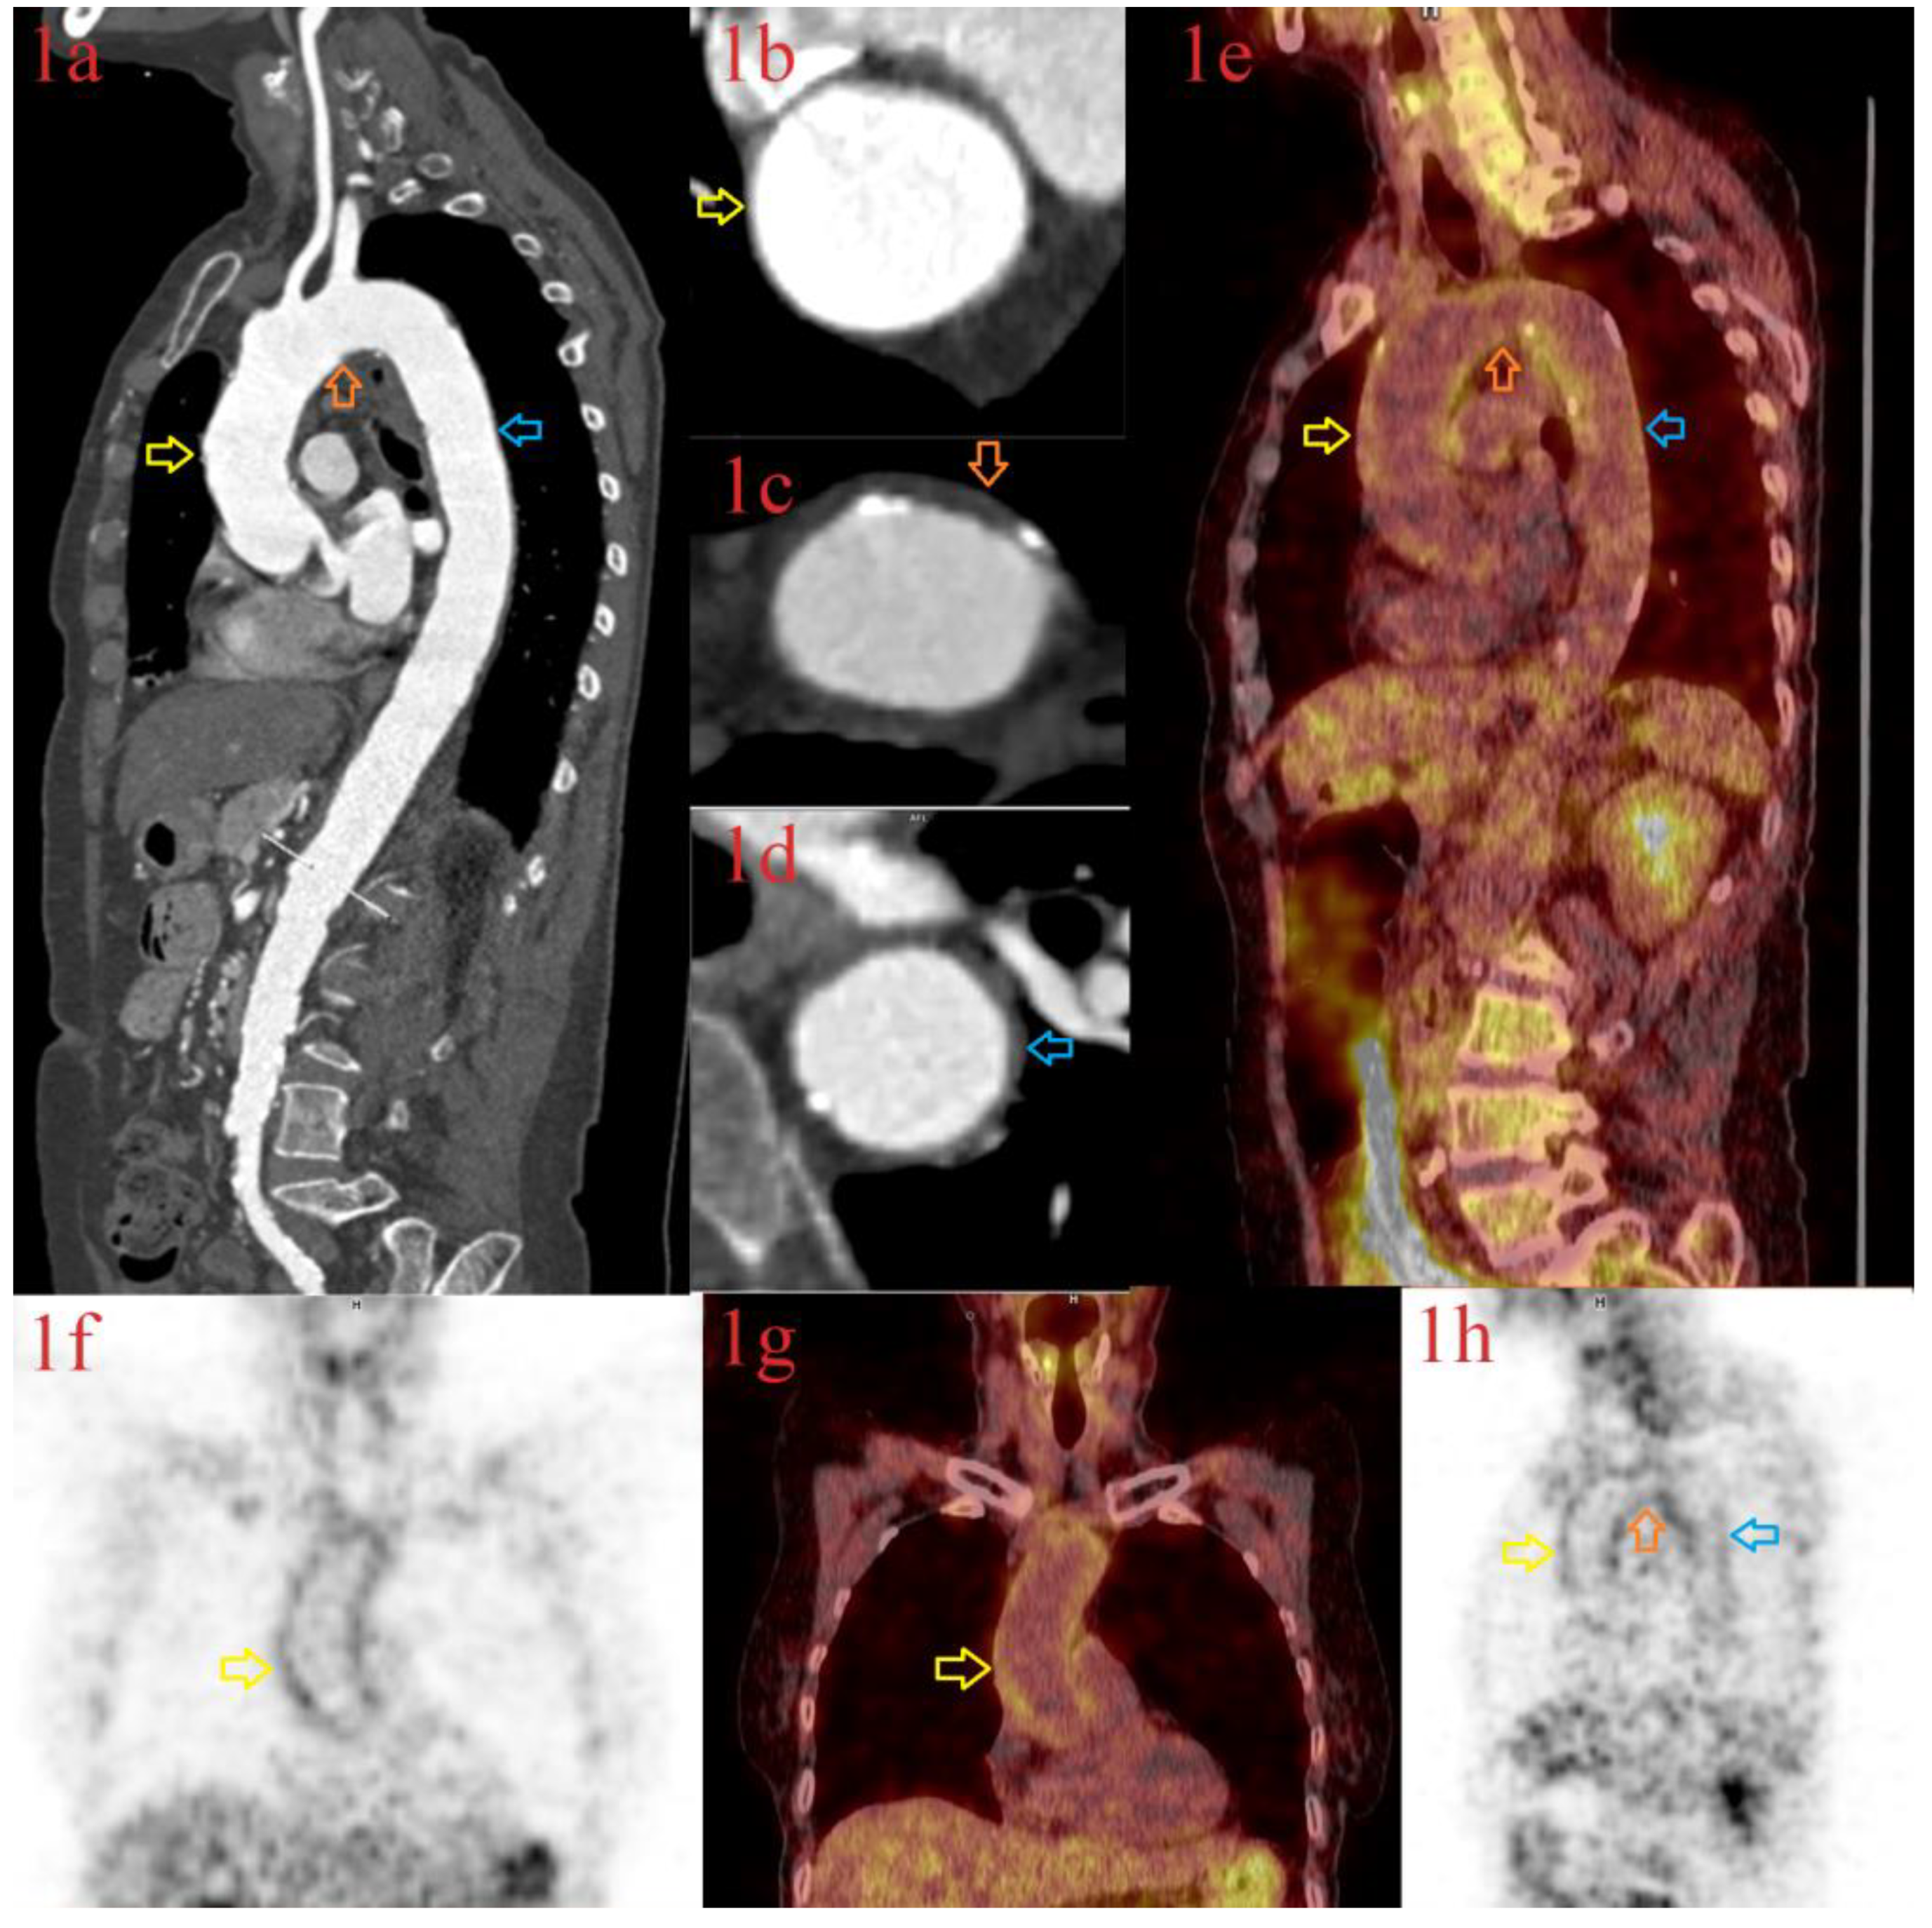

| Ivanovic J, et al., 2022 * [8] | 69 years, male | Headache, fever, elevated ESR, CRP, Fib, IL-6 | 6 weeks | LV-GCA Cerebral vasculitis | High dose CS, TPE Tocilizumab, IVIG, AZA | FDG PET CT Brain MRI | Improvement on treatment |